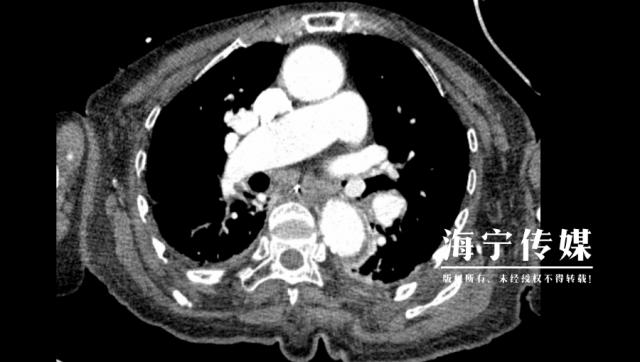

68 年龄较大的徐先生(化名)因慢性肺病反复住院,半个月前刚刚病情稳定出院。但两天前,他突然出现强烈的胸闷、喉咙喘息,CT 发现右边的检查主气管卡在一个直径约一个直径 1.5 类圆形异物厘米。

询问了解到,患者生病前一边吃枇杷一边谈笑风生,误将果核吞入气道。据医院呼吸科主任柳志浩介绍,“果核随着呼吸上下移动,随时可能完全堵塞气道,引起窒息,必须立即在镜下取出。”